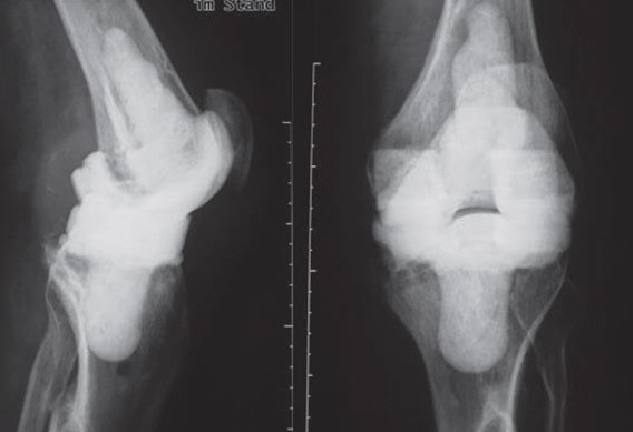

In order to diagnose these infections, tissue samples are taken from the joint in addition to a puncture, as only close cooperation between orthopedists, pathologists and microbiologists can ensure the correct diagnosis. In addition, we also devote ourselves to obviously infected prostheses, of course. These infections can occur shortly after the operation (so-called early infection up to 6 weeks postoperatively) but also years after the operation (as so-called late infection). In addition to the smallest entry points (e.g. an ulcerated toenail), serious infections such as pneumonia can also lead to bacteria colonizing the surface of the prosthesis. Patients with a limited immune system (e.g. diabetics, rheumatics) are particularly at risk. If an infection is noticed early enough after surgery, it is occasionally still possible to eliminate the infection without removing the prosthesis by carefully cleaning the wound and changing the moving parts.

However, infections often go unnoticed for many weeks, so that removal of the prosthesis is unavoidable. Depending on the pathogen and its sensitivity, a placeholder containing antibiotics is then implanted, which remains in place for 6 weeks. Antibiotics in tablet form must then also be taken for this period. However, it is not necessary for a patient to remain in the hospital during this entire period. If home care is not possible, for example, it is also possible to organize this in close cooperation with our social services. After 6 weeks it is generally possible to reimplant a prosthesis, provided that the blood values show that the infection is under control. Antibiotics must then be taken again for 6 weeks after surgery. Which antibiotics are taken is determined in close cooperation with colleagues in microbiology and clinical pharmacology, with whom regular rounds and therapy checks are carried out. These therapeutic measures are carried out in a special area of the clinic using the most modern methods.

Infizierte HüfttotalendoprotheseKniegelenkinfektion nach EndoprotheseImplantierte Spacer nach ProthesenentfernungVorgefertigte Spacer (Platzhalter) mit Antibiotika